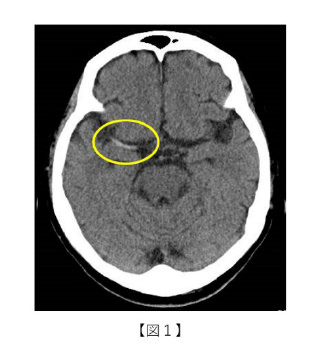

IC-PC動脈瘤との鑑別がしばしば問題となるのが漏斗状拡張 infundibular dilatation です。 鑑別のポイントは ▷漏斗状拡張は先端から動脈分枝が出ている→MIP像やMPR画像を作成▷動脈瘤は後外側下方に向かい、漏斗状拡張は先端部が内側向きに出ることが多い。 という点です。

内頸動脈・後交通動脈分岐部漏斗状拡張を思わせる小動脈瘤破裂の2例Neurological Surgery 脳神経外科 8巻6号医書.jp。

infundibular dilatation脳疾患を知る桑名眼科脳神経クリニック。

脳動脈瘤の画像診断と撮影法ー破裂リスクの評価と漏斗状拡張との鑑別。